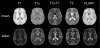

STAMP atlases include 4 modalities (T1, T2, T1c, FLAIR) and 1 artificial modality (T1d:=T1c-T1, highlighting pure contrast). Here T1c is T1 MRI with gadolinium contrast. Multi-modal atlases help detect lesion components. The otherwise rarely available T1c/T1d atlases can help differentiate between normal vessels and enhancing tumor, both enhancing upon gadolinium injection.